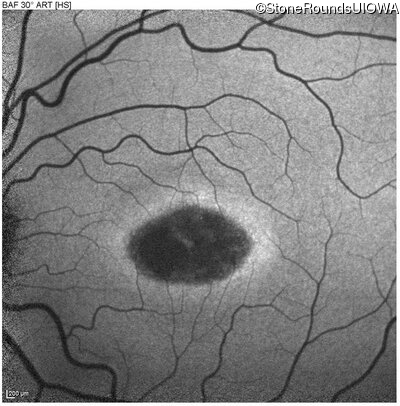

Blue Autofluorescence - Left - 20/25 -1 sc

Exemplar